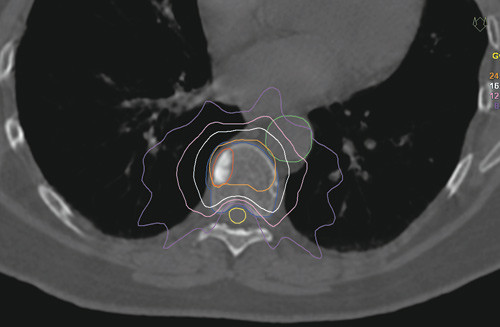

Stereotaktisk strålebehandling er en avansert behandlingsform som de siste årene har økt betydelig i omfang og anvendelsesområder. Man bruker det samme utstyret og prinsippene som ved ordinær strålebehandling, men det leveres en høypresis behandling mot små områder, og man oppnår en skarpere avgrensning mellom det som skal bestråles og områder som bør unngås. Dette gjøres bl.a. ved å benytte mange feltinnganger og ekstra god fiksering av pasienten. Et eksempel på et slikt feltarrangement er vist i figur 2. Strålingsdosene ved stereotaktisk strålebehandling er vanligvis mye høyere enn for konvensjonelle behandlinger og kan leveres på ett eller få oppmøter for pasienten. Vanlig dose kan her være opptil 25 Gy gitt som en engangsbehandling. Dette tilsvarer en langt høyere dose enn det som gis med fraksjonert behandling, siden den biologiske effekten ikke bare har sammenheng med totaldose, men også dose per fraksjon (7).

Vi tilbyr nå behandling hvor den beregnede dosefordelingen er ekvivalent med høyavansert stereotaktisk behandling, mens planleggingsfasen er sammenliknbar med de enkle konvensjonelle metodene når det gjelder ressursbruk. Et vesentlig moment er at den beregnede dosen til medulla må holdes på et minimum, mens dosen til virvelen som behandles må være høy nok til å gi varig lokal effekt. Løsningen ble å lage et templatbasert behandlingsopplegg, altså et opplegg som i utgangspunktet er uavhengig av den enkelte pasient, men som med små justeringer kan tilpasses pasienten. Behandlingen gis med ni standardiserte feltvinkler, som gjør at strålingsdosen blir fordelt utenom medulla (fig 2). Resultatet ble en planleggingsprosess som i de fleste tilfeller tar 15 – 30 minutter, mens de mest vanlige planleggingsprotokollene ville krevd flere timer.

Den beregnede dosefordelingen gir betydelig høyere svulstdose, og en tilfredsstillende skjerming av risikoorganene i nærheten av behandlingsområdet, sett i forhold til konvensjonell behandling. Tumorområdet får over 18 Gy (midlere strålingsdose 24 Gy), mens medulla får maksimalt 12 Gy. Til sammenlikning er dosefordelingen fra et tradisjonelt opplegg, der 30 Gy gis i ti fraksjoner, vist i figur 1.